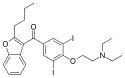

| Formula | C25H29I2NO3 |

| Molar mass | 645.320 g·mol−1 |

Amiodarone may be an acronym for its IUPAC name (2-butyl-1-benzofuran-3-yl)-[4-[2-(diethylamino)ethoxy]-3,5-diiodophenyl]methanone,[62] where ar is a placeholder for phenyl. This is partially supported by dronedarone which is noniodinated benzofuran derivative of amiodarone, where the arylmethanone is conserved.